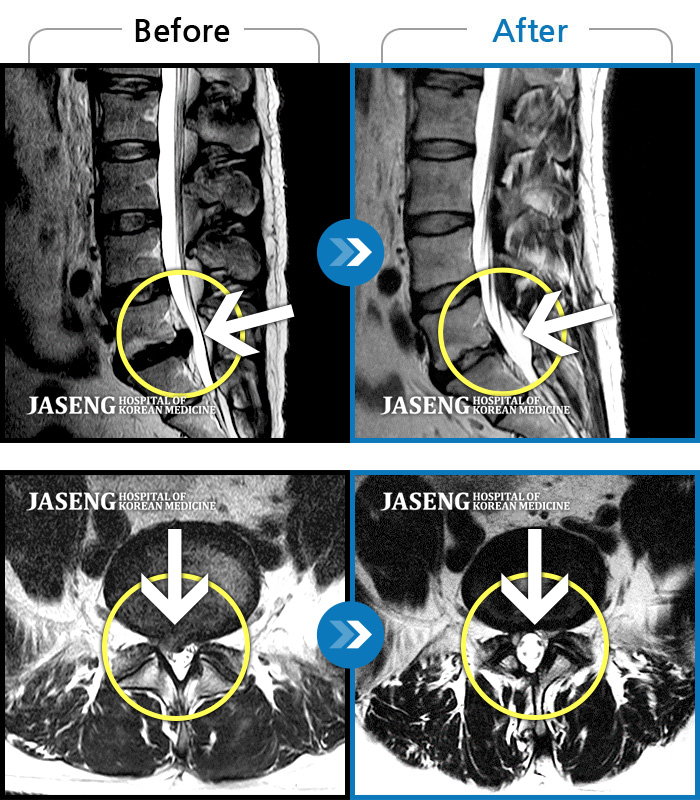

처음 내원 시 허리와 좌측 골반이 많이 아프고, 좌측 다리로 저림과 감각 저하가 있어서 보행이 원활하지 못했으며, 야간통으로 잠도 못 자고 통증 심하여 정상적인 활동이 힘든 상태셨습니다.

2023.09.16 ~ 2024.09.24